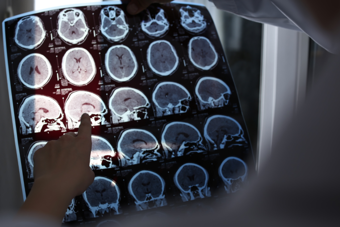

We’re seeking greater understanding of the genetics and pathophysiology of diseases of the brain and nervous system, and improving the diagnosis and surgical, medical and psychological management of neurological disease, intellectual disability and cognitive health.

Neuroimmunology and Stroke Research